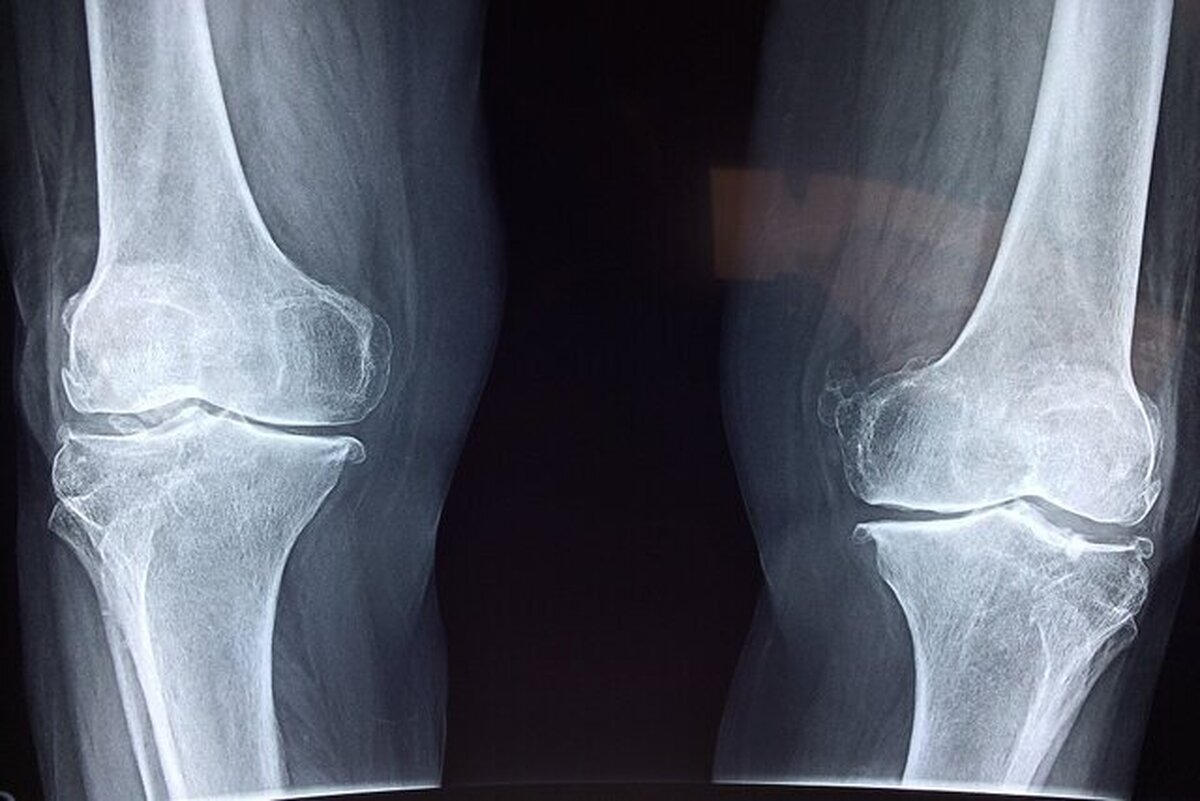

آسیب به استخوان‌ها

نخستین نگرانی، تاثیر منفی بر سلامت استخوان‌هاست. مصرف نوشابه و الکل هر دو با کاهش تراکم مواد معدنی استخوان و افزایش خطر شکستگی مرتبط است. مصرف نوشابه به‌دلیل وجود اسید فسفریک می‌تواند تعادل کلسیم و فسفر را بر هم بزند و خطر شکستگی لگن را افزایش دهد. مصرف الکل نیز با کمبود کلسیم، اختلال‌های کبدی و کاهش ویتامین دی همراه است که همگی به تضعیف استخوان‌ها منجر می‌شوند.